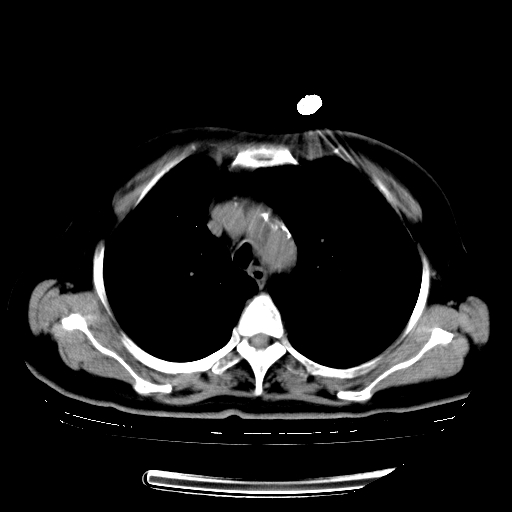

女,70岁,咳嗽、咳痰一个月,低热一周。

1.左上肺结核,部分纤维化。右肺中下叶部分肺不张,内见液化、坏死及点状钙化,右中下叶支气管壁增厚、管腔狭窄,见多个点状钙化,结合临床考虑支气管内膜结核,建议痰检查抗酸杆菌并参考血沉。两肺多个小圆点状高密度灶,境界模糊,多考虑结核肺内播散。但本人年龄较大首先应支气管镜检以除外右肺癌。

2.胸主动脉夹层。